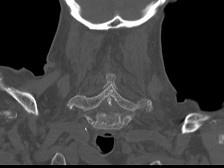

问题 男,92岁,下腰不适伴晨僵半年余,请结合影像学检查,选出最可能的诊断 ( )

选项 A、阻滞椎 B、类风湿关节炎 C、强直性脊柱炎 D、化脓性脊柱炎 E、脊椎退行性变

答案 C